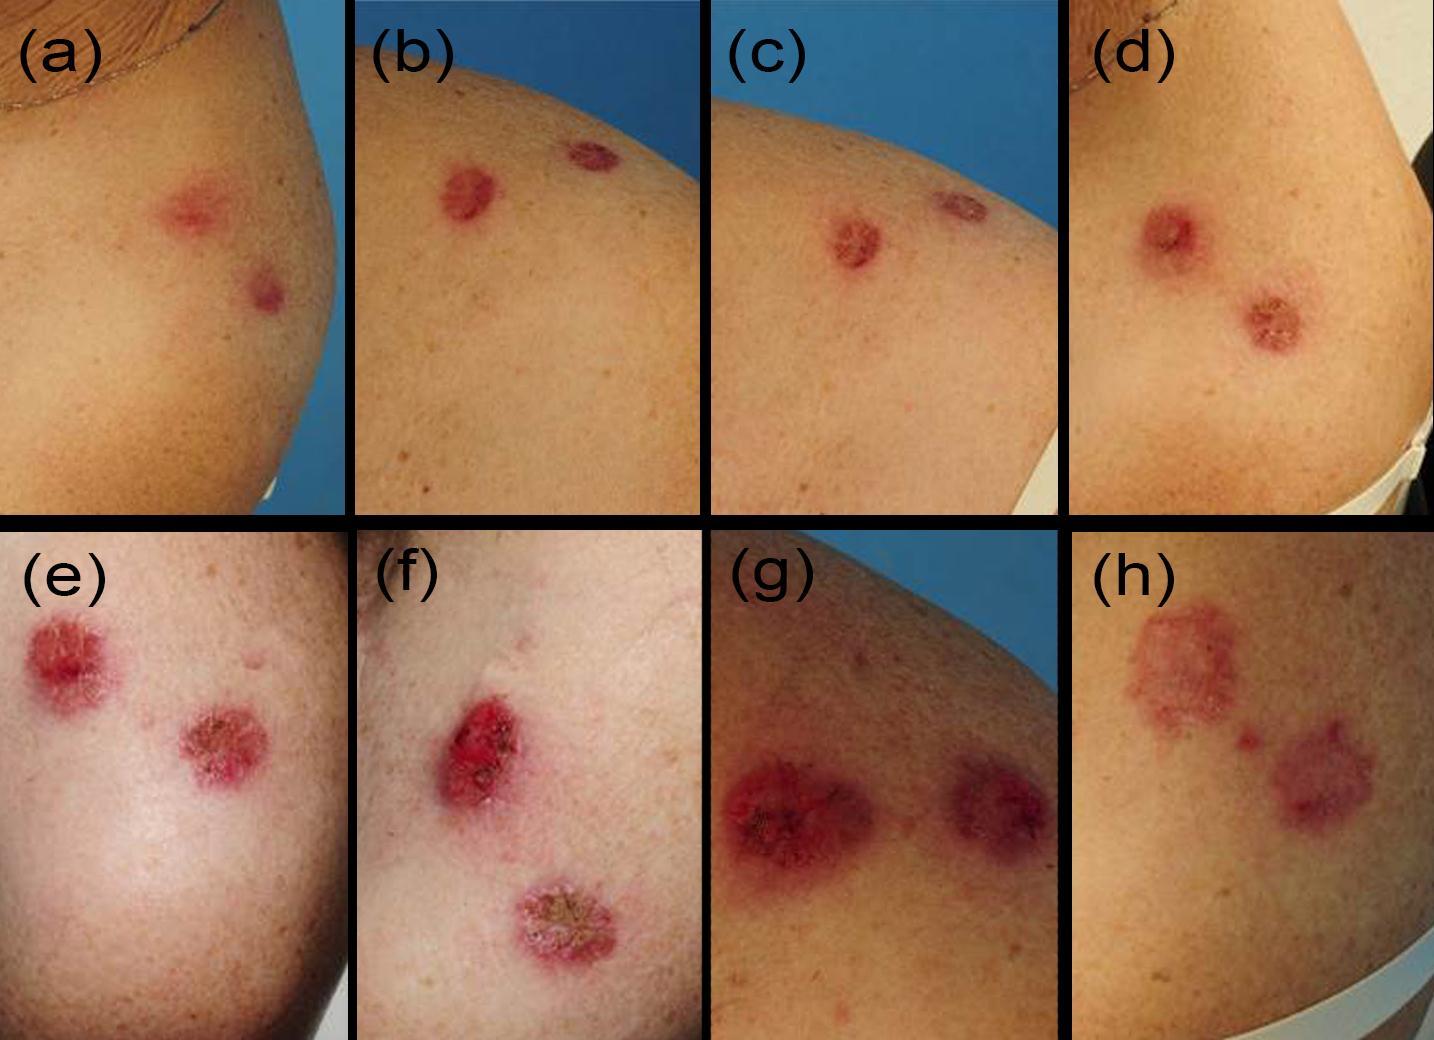

Figure 5.Sequence of the typical therapeutic skin reactions in an arm 3 basal cell carcinoma patient at all visits: Days 0, 2, 4, 7, 9, 11, 13, 20 (a-h)

In contrast to IQM alone, the combined use of the fractionated erbium:YAG laser microporation with IQM dominantly induced stronger skin erythema levels starting from visit V2 throughout the last visit V20 (Figure 3a). For the stronger therapeutic responses of crusting and erosions this phenomenon was even more pronounced. By looking at the mean crusting PGA values of V2, V4 and V7 together as early time point of the therapy, arm 2-4 presented with the scores of 0.76±0.3, 1.25±0.2 and 1.3±0.5 compared to the much less pronounced value of crusting in the single IQM control arm-1 with 0.3±0.2. The same is true for the late therapy time point V9/11/13/20 with crusting 2.25±0.8, 2.5±0.5 and 2.3±0.4 arms 2-4 and only 1.3±0.6 in the control arm. For erosions the following mean PGA scores were delineated: V2/4/7 arm 1-4 0.08±0.1, 0.6±0.3, 0.75±0.2, 0.95±0.5 and V9/11/13/20 arm 1-4: 0.5±0.25, 1.2±0.6, 1.37±0.3, 1.44±0.4. Regarding the IQM skin responses no correlation could be found with the amount of shots and pulses used by the laser device. Histopathology of V20 lesional punch biopsies showed in all BCC a dense infiltrate of inflammatory cells which is typical for an adequate IQM response. When this infiltrate was fully replacing signs of BCC the lesions were defined as fully cleared (Figure 4). Within arm 2-4 BCC lesions cleared at 33% (persistent 1 nodular and 1 superficial BCC), 100% and 100% at V20, respectively. Taken together IQM alone led to clearence of 3 out of 4 (75%, persistent a superficial) BCC, though the treatment period was shortened from 6 to 3 weeks. The combined fractionated erbium:YAG laser and IQM application resulted in a slightly better clearance rate of 14 BCC vs. 4 (78%). Notably, those 2 BCC patients, where the laser and IQM application was stopped at V11 also showed full clearence. Figure 5 presents the typical treatment course of a patient in arm 3. Tolerability of the laser microporation was excellent with slight burning or the feeling of small needle sticks during the application. In addition, microporation did not cause any immediate irritation of the skin. Even when erythematous, crusted or eroded IQM lesions were microporated the good tolerability stayed the same. No severe adverse or adverse reactions were noted.